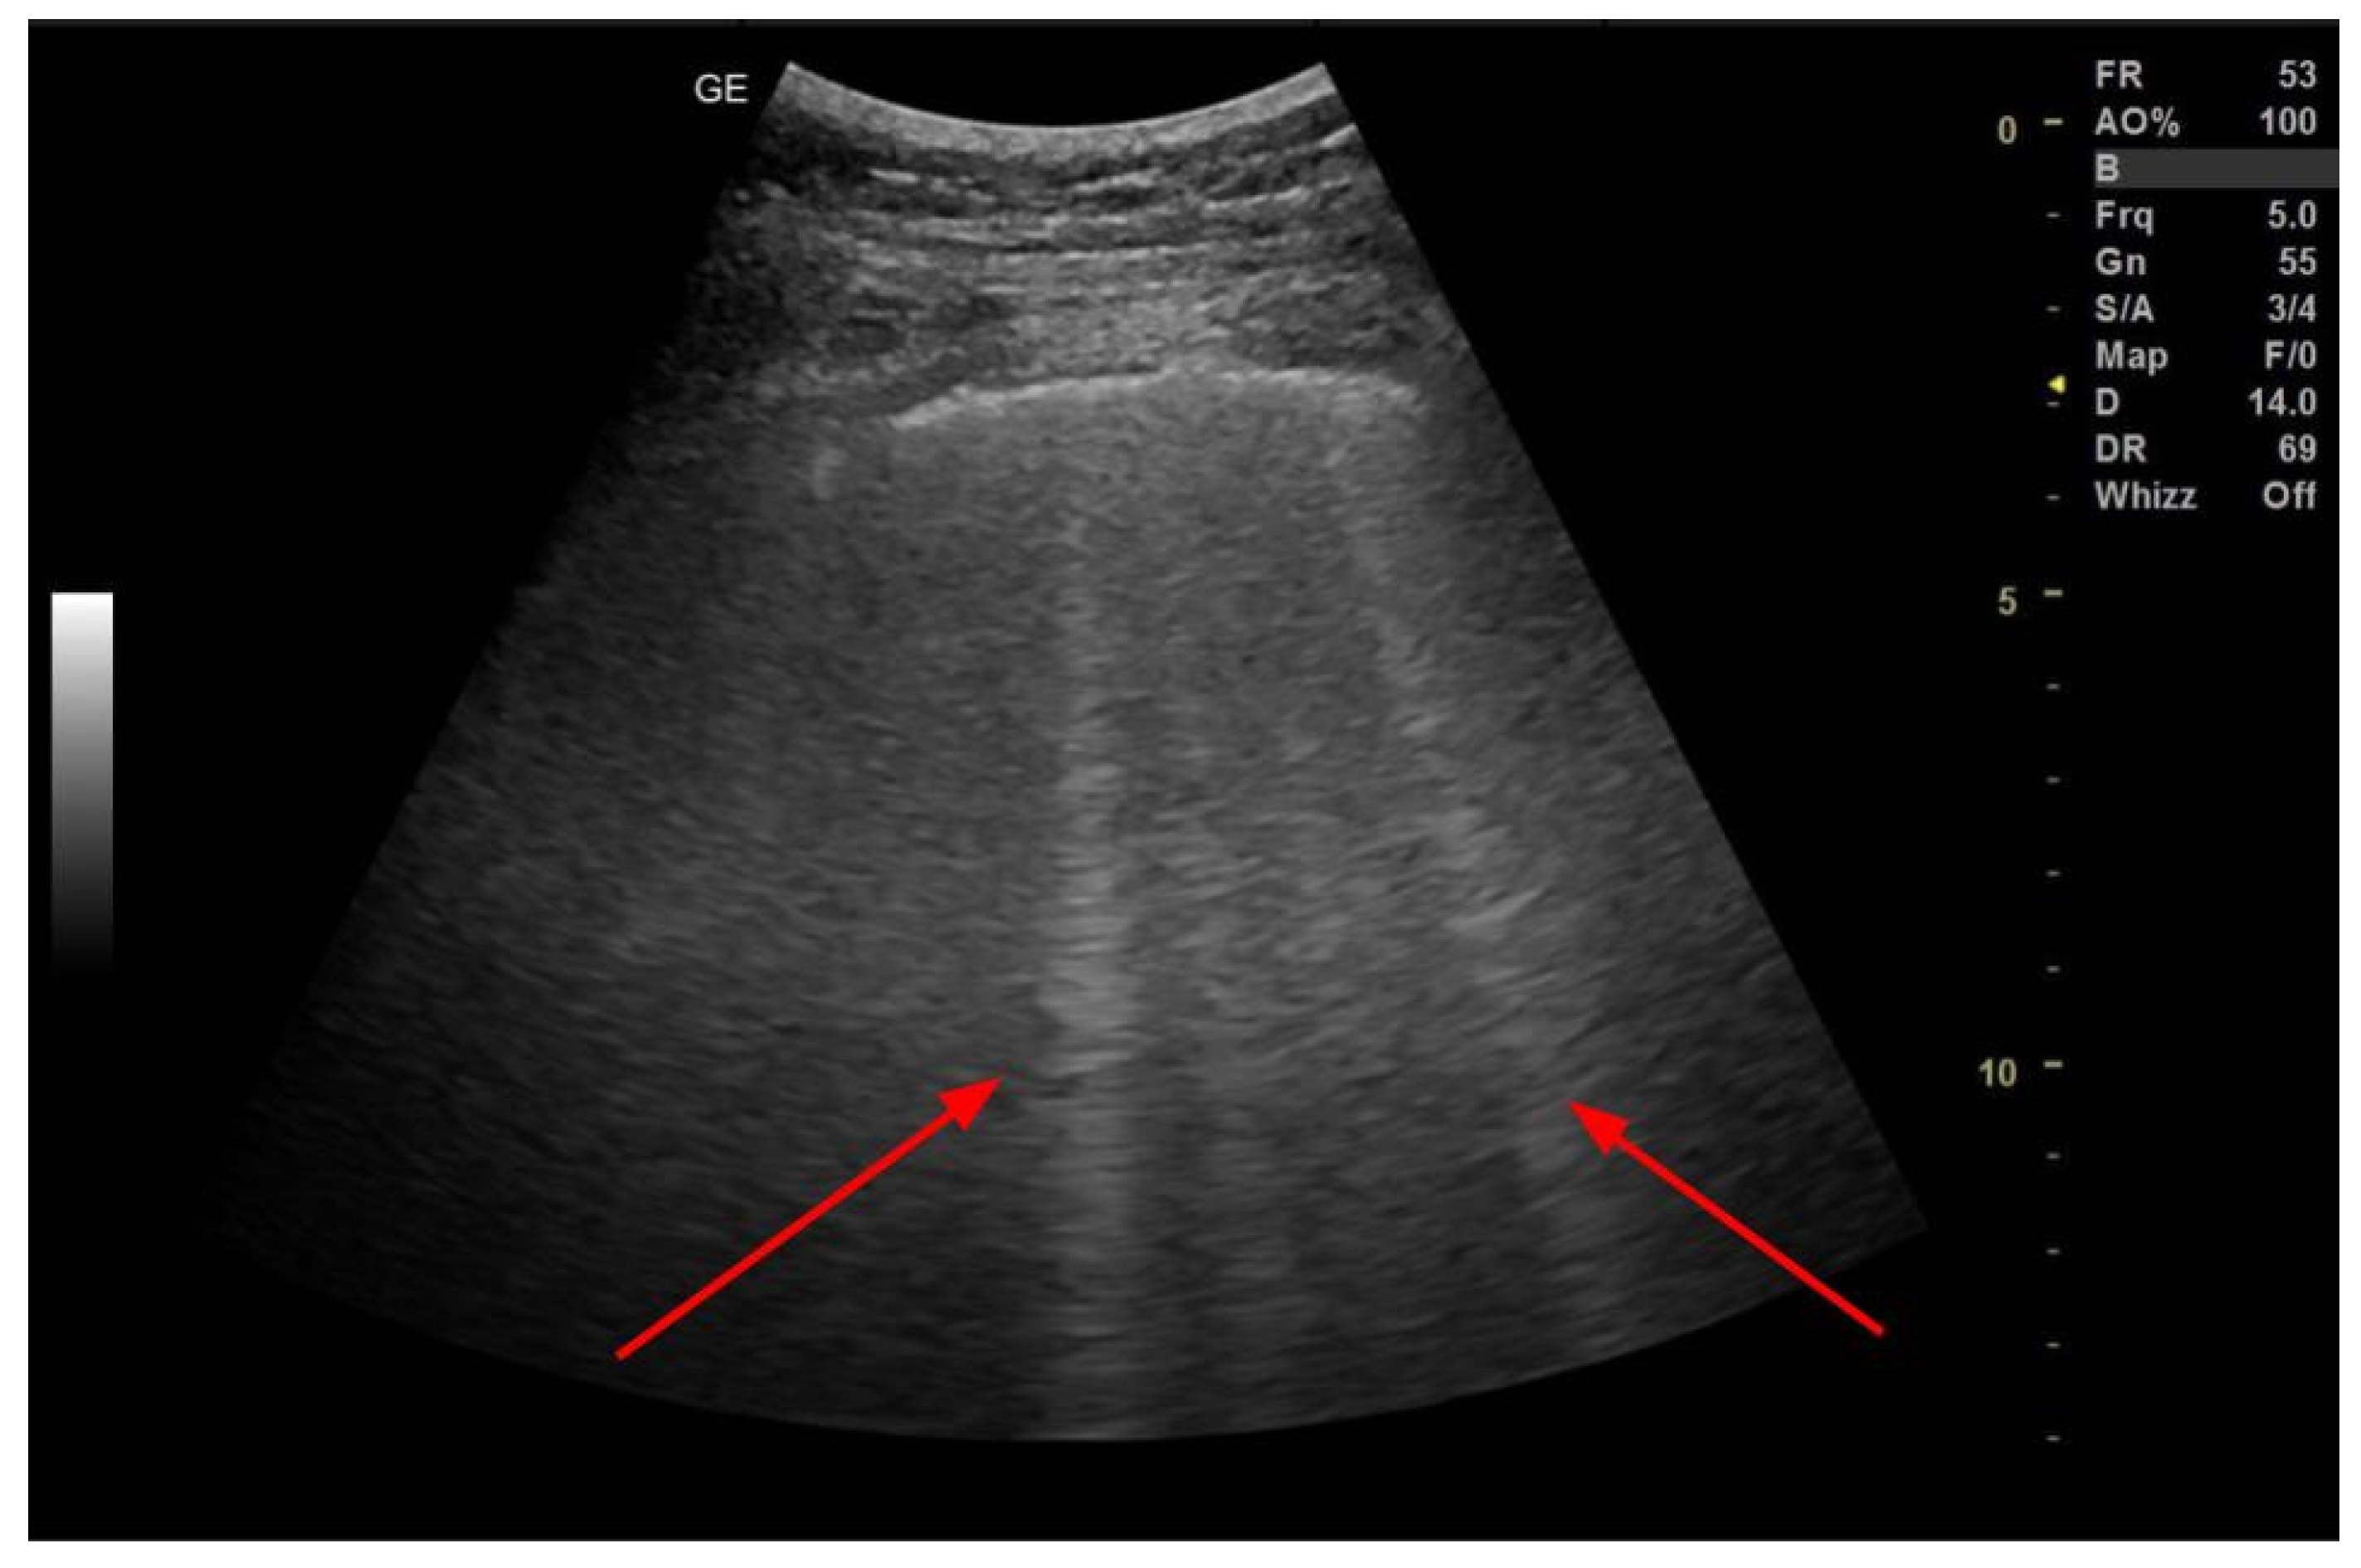

3.3. Pleural Effusion

- Hassan, M.; Rizk, R.; Essam, H.; Abouelnour, A. Validation of Equations for Pleural Effusion Volume Estimation by Ultrasonography. J. Ultrasound 2017, 20, 267–271. [Google Scholar] [CrossRef]